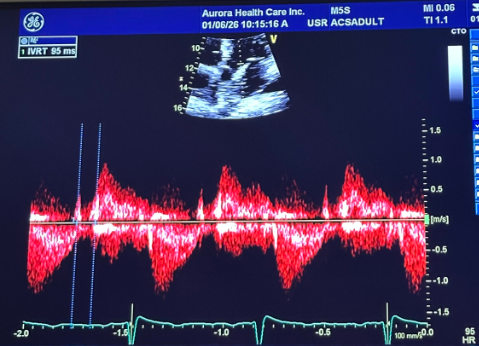

what is the measurement for

this is going to be the RV systolic function, this is the TAPSE measurement from the bottom of the hill to the top of the hill the normal values for TAPSE is >1.7- <2.4

what is the measuring

This is our S’, should be >9.5